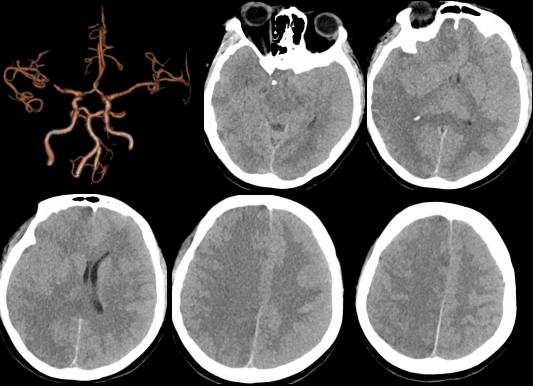

新冠疫情来势汹汹,整个城市按下暂停键。然而疾病的发生率并没有因为疫情肆虐而降低。在这特殊时期,重医附二院神经外科救治急危重症患者的脚步一刻也没有停歇,生死交织的序曲每天都在上演。患者重度昏迷 命悬一线